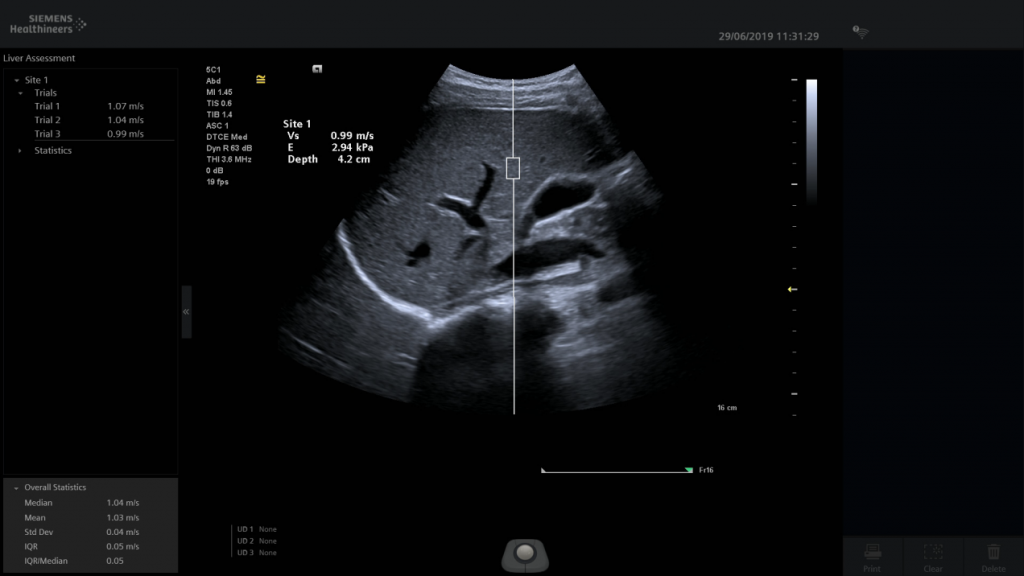

Hình 1. Hình ảnh trên siêu âm đàn hồi mô

• Siêu âm đàn hồi mô gan: Xác định mức độ xơ hóa gan trên các đối tượng có yếu tố nguy cơ cao dẫn đến xơ gan hay ung thư gan như: viêm gan virus B, Virus C, gan nhiễm mỡ do rượu, một số bệnh chuyển hóa ảnh hưởng đến gan. Đây là kỹ thuật sử dụng để đánh giá độ cứng của nhu mô gan, độ cứng của gan liên quan đến mức độ xơ hoá. Kết quả có ngay, nó cho thấy tình trạng của gan, cho phép các thầy thuốc chẩn đoán và theo dõi tiến triển của bệnh cùng với tiến trình điều trị. Đây là một kỹ thuật mới có hiệu quả cao trong việc tầm soát và chẩn đoán bệnh xơ gan. Khi làm siêu âm B mode thấy có tổn thương khu trú trong nhu mô gan, căn cứ vào tính chất phản âm đồng nhất hay không đồng nhất, bờ của tổn thương có ranh giới rõ hay không rõ, đều hay không đều, dày hay mỏng… cho phép nhận định sơ bộ bản chất của tổn thương. Dùng siêu âm Doppler cho phép nhận định mức độ tưới máu của tổn thương, nếu tăng tưới máu thường là u ác. Dùng siêu âm đàn hồi mô xác định độ cứng, nếu là score 4 thì là u ác tính, nếu là score 1 thì là tổn thương lành tính, nếu là score 2,3 thì là nghi ngờ, cần căn cứ thêm các yếu tố khác: nếu có tăng tưới máu thì nghiêng về u ác, nếu không tăng tưới máu, diện tích trên Elastogram không lớn hơn diện tích trên B mode thì cần xác định thêm bằng sinh thiết.